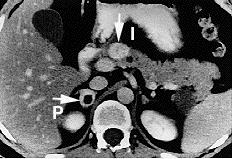

194. Multiple endocring neoplasia type 2; Bilateral pheochromocytomas associated with multiple endocrine neoplasia type 2 http://en.wikipedia.org/wiki/Multiple_endocrine_neoplasia_type_2 ; http://en.wikipedia.org/wiki/File:Bilateral_pheo_MEN2.jpg . public domain image.

195. Pheochromocytoma, public domain, http://en.wikipedia.org/wiki/File:Pheochromocytoma.jpg . (Choyke PL Glenn  GM Walther W Patronas NJ Linehan WM Zbar B, Radiology (March) 146: 629-642, 1995, http://www.cc.nih.gov/ccc/papers/vonhip/adrenal.html .)

196. Fitzgerald PA Adrenal Medulla & Paraganglia (Chapter 12) in Greenspan's Basic & Clinical Endocrinology, 8th edition, Gardner DB and Shoback D, eds, on-line edition, The McGraw-Hill Companies, 2007.